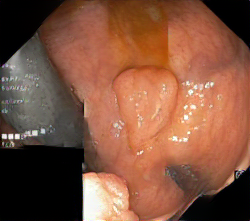

We have used a polyp dataset published with HyperKvasir dataset [51], which consists of polyp findings extracted from endoscopy examinations. HyperKvasir contains polyp images with corresponding segmentation masks annotated by medical experts. We use only this polyp dataset as a case study because of the time and resource-consuming training process of the SinGAN-Seg pipeline. However, the SinGAN-Seg model and pipeline can be used for any segmentation dataset.

A few sample images and the corresponding masks of the polyp dataset in HyperKvasir are shown in Fig 2. The polyp images are RGB images. The masks of the polyp images are single-channel images with white () for true pixels, which represent polyp regions, and black () for false pixels, which represent clean colon or background regions. In this dataset, there are different sizes of polyps. The distribution of polyp sizes as a percentage of the full image size is presented in the histogram plot in Fig 3, and we can observe that there are more relatively small polyps compared to larger polyps. Additionally, a subset of this dataset was used to prove that the performance of segmentation models trained with small datasets can be improved using our SinGAN-Seg pipeline, and the whole dataset was used to show the effect of using SinGAN-Seg generated synthetic images instead of a large dataset which has enough data to train segmentation models. In this regard, this dataset was used for two purposes: